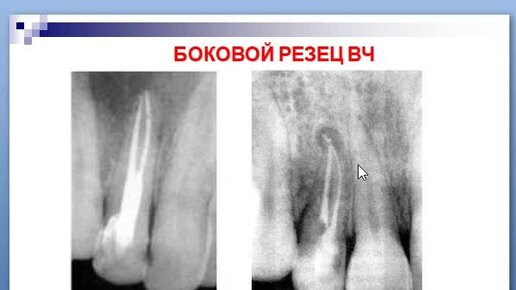

9:50 №26 Введение в эндодонтию. Топографо-морфологическая характеристика полости зуб